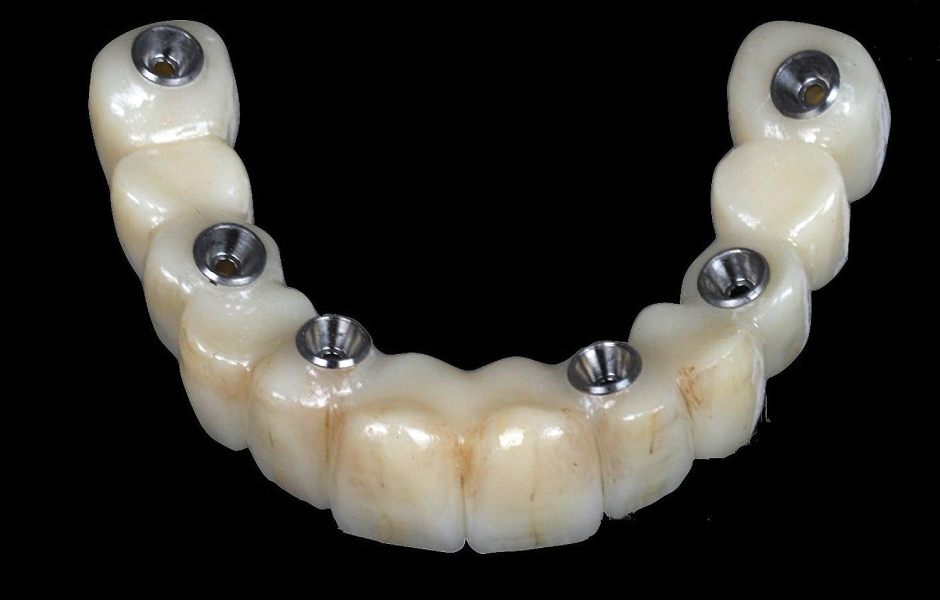

Pro kotvení definitivní náhrady byly použity abutmenty Variobase® for Bridge. Materiálem pro výrobu definitivní náhrady byl zvolen monolitický zirkon (obr. 49, 50).

Obr. 49

Obr. 50